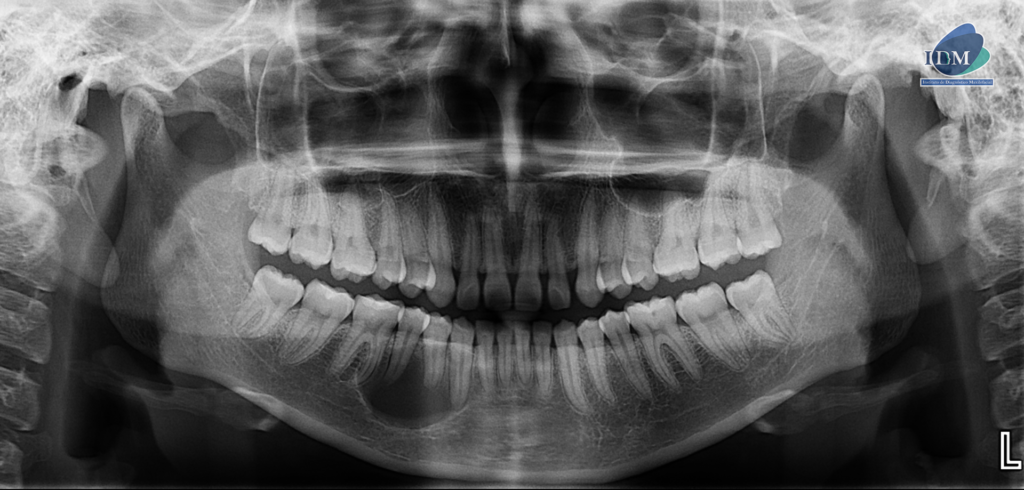

En la radiografía panorámica (Figura 1), se aprecia imagen radiolúcida unilocular, proyectada en cuerpo mandibular derecho, de limites definidos, bordes parcialmente corticalizados.

Radiografia Panorámica